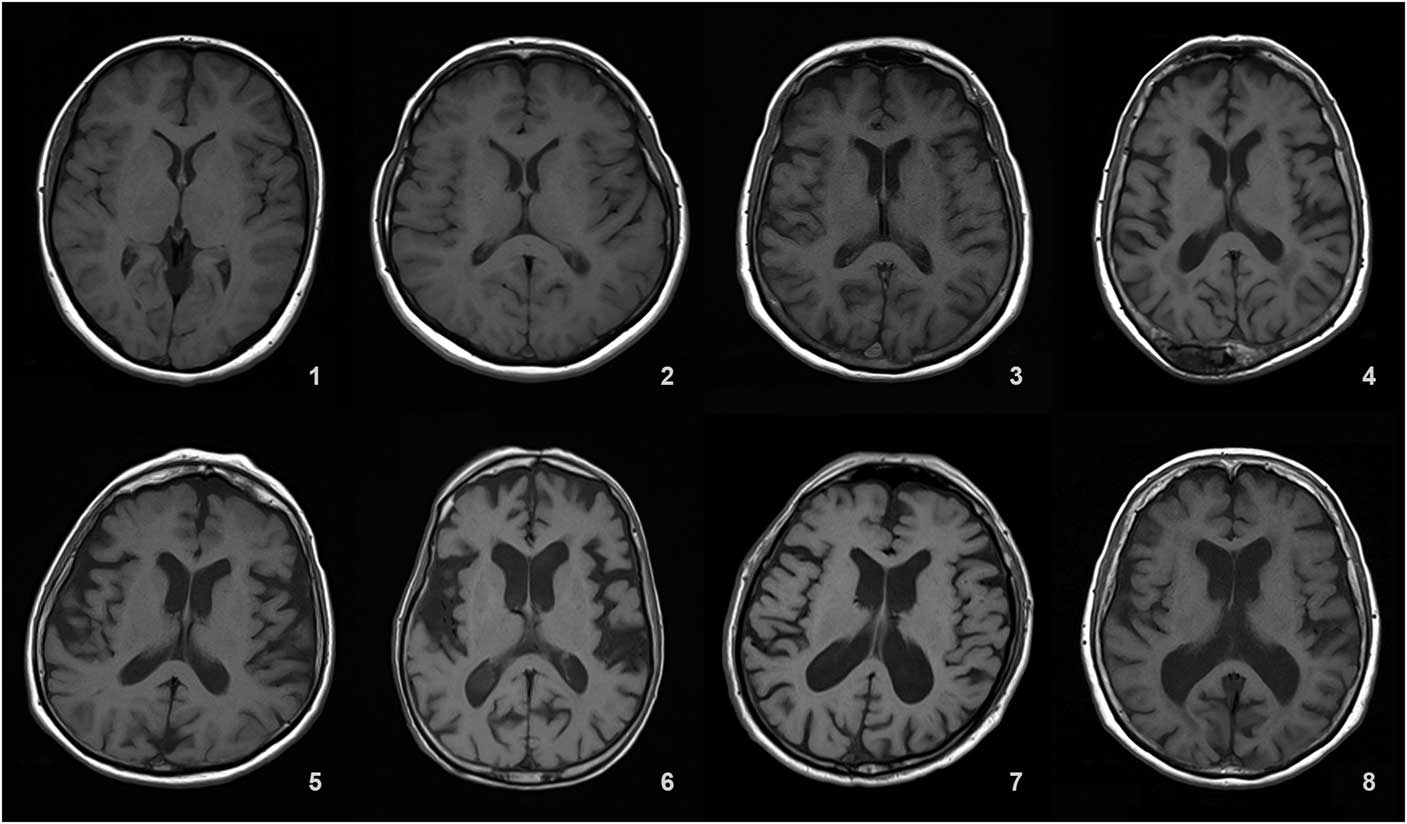

Ventricular atrophy (VA) was graded in a 0-9 range on the axial T1 (TR=673 ms, TE=12 ms, 3 or 5 mm slice thickness, 0.6 mm gap) slice showing the frontal and occipital horns of the lateral ventricles together with the third ventricle.

Details of the proposed scale are given in Table 1. For grading the SA, VA, and MTA, a reference data set was created from cranial MRIs of 30 subjects who were admitted to the clinic owing to complaints other than forgetfulness, but they were not included in the study (Figures 1–3). An exemplary MRI scan of a patient graded with PWMH=4 and SCWMH=3 can be seen in Figure 4.

Figure 2 Reference MRIs corresponding to ventricular atrophy grades between 1-8.